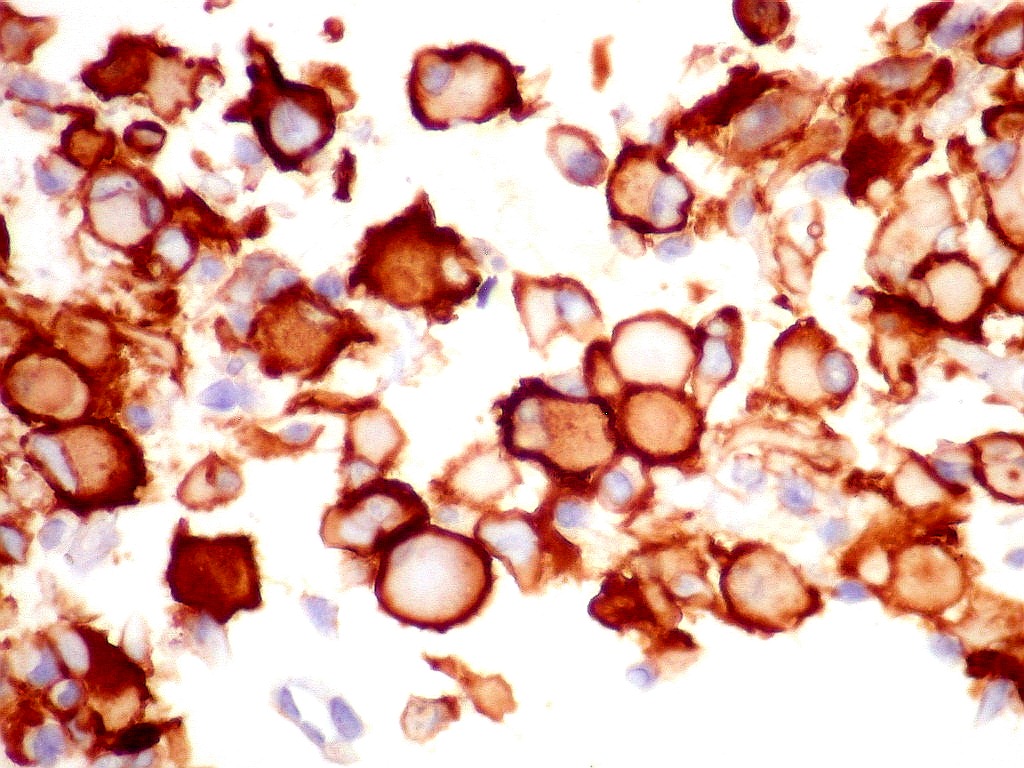

S-100.   Proteína S100 é expressa em células originadas da crista neural, como melanócitos e células de Schwann, e em macrófagos.  Aqui é observada em parte das células tumorais, em positividade nuclear e citoplasmática.